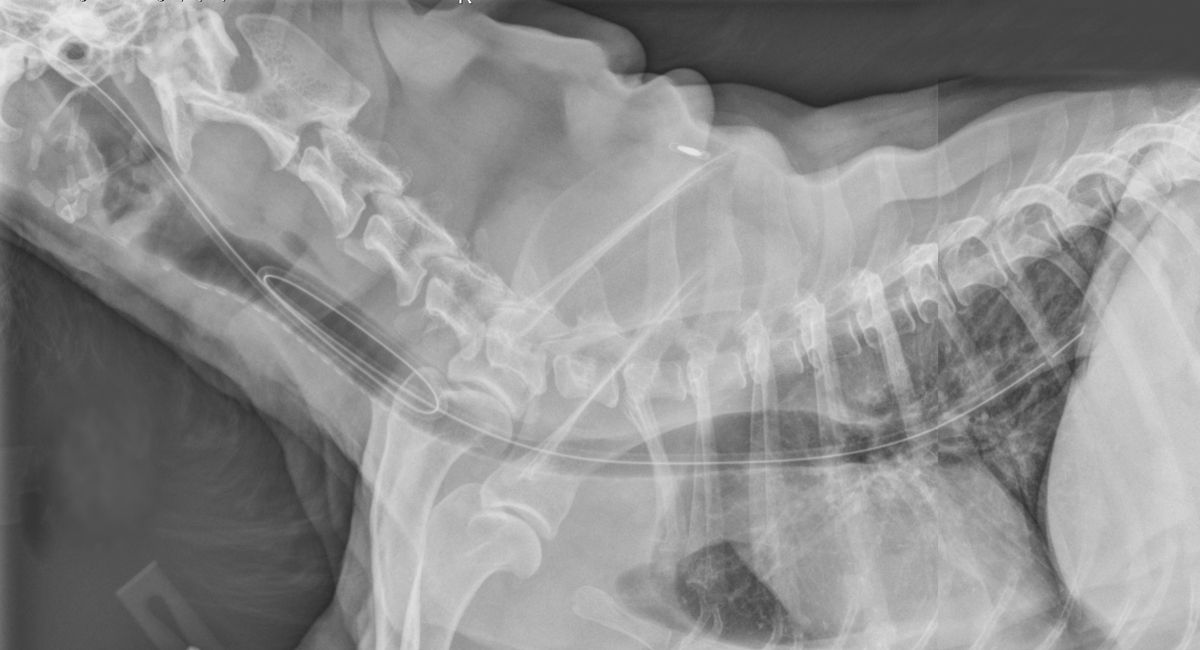

Feeding Tubes In Small Animals at Paul Gonzales blog How Long Can A Dog Have A Feeding Tube A feeding tube is a flexible length of piping that allows food to be directly placed into an animal's stomach or intestinal tract. Feeding tubes are generally recommended when a pet has not eaten in three or more days. The tubes can be used to provide food, water, and even medications. A guide to using nasal feeding tubes in dogs:. How Long Can A Dog Have A Feeding Tube.